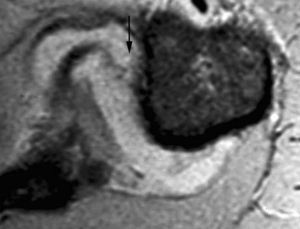

Lesión de Bankart

La lesión de Bankart se produce durante una dislocación anterior e inferior de la cabeza humeral, con impactación de la misma contra el borde anteroinferior de la glenoides, causando un arrancamiento del LG con rotura capsuloperióstica. Al mismo tiempo, se produce frecuentemente una fractura por impactación de la cabeza humeral (lesión de Hill Sachs) (fig. 9). En ocasiones, dicha lesión se acompaña de una fractura del borde anterior e inferior de la glenoides (Bankart óseo).

Fig. 9.--Lesión de Bankard y Hill-Sachs. Artrorresonancia axial T1, donde se observa un desprendimiento completo del labio glenoideo (flecha larga en A) con una rotura capsuloperióstica (cabezas de flecha en A). Nótese la fractura por compresión del margen posterosuperior de la cabeza humeral, representando una lesión de Hill-Sachs (flechas en B).